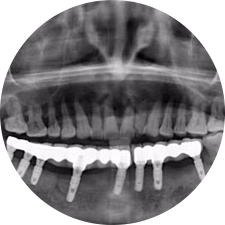

河北惟德口腔醫(yī)院擁有國內(nèi)豐富的半口/全口、即刻負(fù)重種植案例,十八年案例跟蹤分析,總結(jié)梳理出的各種不同類型的種植案例,Nobel種植體系針對(duì)半口/全口缺牙患者,通過4-8顆種植體可快速達(dá)到牙齒重建,不僅植入種植體較少,節(jié)省費(fèi)用,手術(shù)時(shí)間更短。

術(shù)前患者CBCT口掃1:1三維重建,模擬手術(shù)過程及預(yù)測(cè)術(shù)后治療效果,確定每顆植體植入的適合的種植位點(diǎn)、深度及角度,有效避免損傷頜骨重要解剖結(jié)構(gòu),提高手術(shù)準(zhǔn)確度與安全性。

惟德口腔種植體系是以患者感受為中心,取代傳統(tǒng)種植牙手術(shù)需要翻瓣、打孔、縫合,術(shù)前、術(shù)中、術(shù)后的繁復(fù)流程,采用3D導(dǎo)航微創(chuàng)準(zhǔn)確種植技術(shù),通過數(shù)字化CAD/CAM掃描技術(shù)獲得缺牙患者口腔數(shù)據(jù),以數(shù)據(jù)為基礎(chǔ)重建口腔模型進(jìn)行模擬種植。

術(shù)前將患者口內(nèi)的CBCT數(shù)據(jù)及咬合關(guān)系上傳到計(jì)算機(jī)中,建立1:1三維重建,模擬手術(shù)過程及預(yù)測(cè)術(shù)后治療效果,找出較佳種植位點(diǎn)、深度及角度,獲取實(shí)際種植體在頜骨內(nèi)的具體三維位置,有效避免損傷頜骨重要解剖結(jié)構(gòu),大大降低手術(shù)風(fēng)險(xiǎn),提升種植成功率。